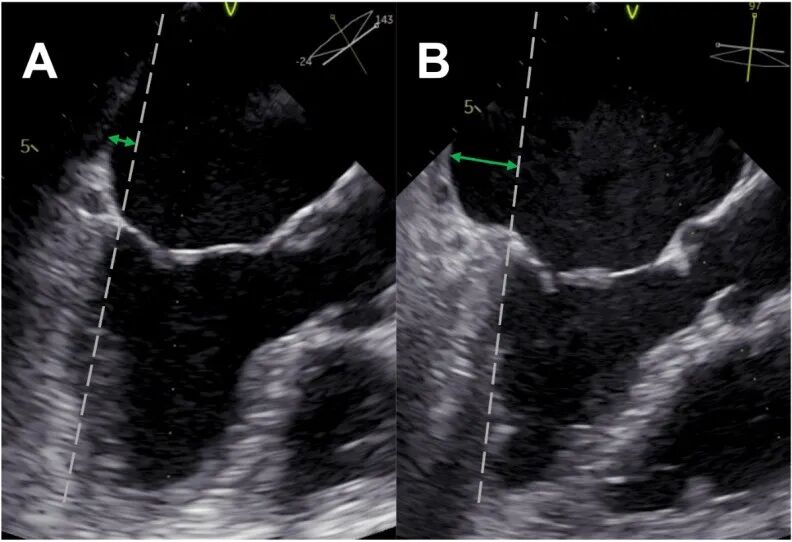

目前,常见的AFMR机制为单纯瓣环扩张导致对合不良(Carpentier I型,即Isolated mitral annulus dilation,IAD),近研究描述了一种新的病理亚型——“房性束缚型”(Atriogenic hamstringing,AH)(有的研究称其为心房源性瓣叶栓系,Atriogenic leaflet tethering,ALT)。该亚型表现为:左心房向后持续扩张,超越了左心室后壁;导致后侧瓣环向外突出;进而牵拉后叶限制其运动,后叶呈现类似Carpentier IIIb型。(如图1)

图1 图中A为AFMR-IAD型,B为AFMR-AH型,显示在中期收缩时,测量左心室心肌(灰色虚线)延长线与左心房后壁(绿色双箭头)之间的距离